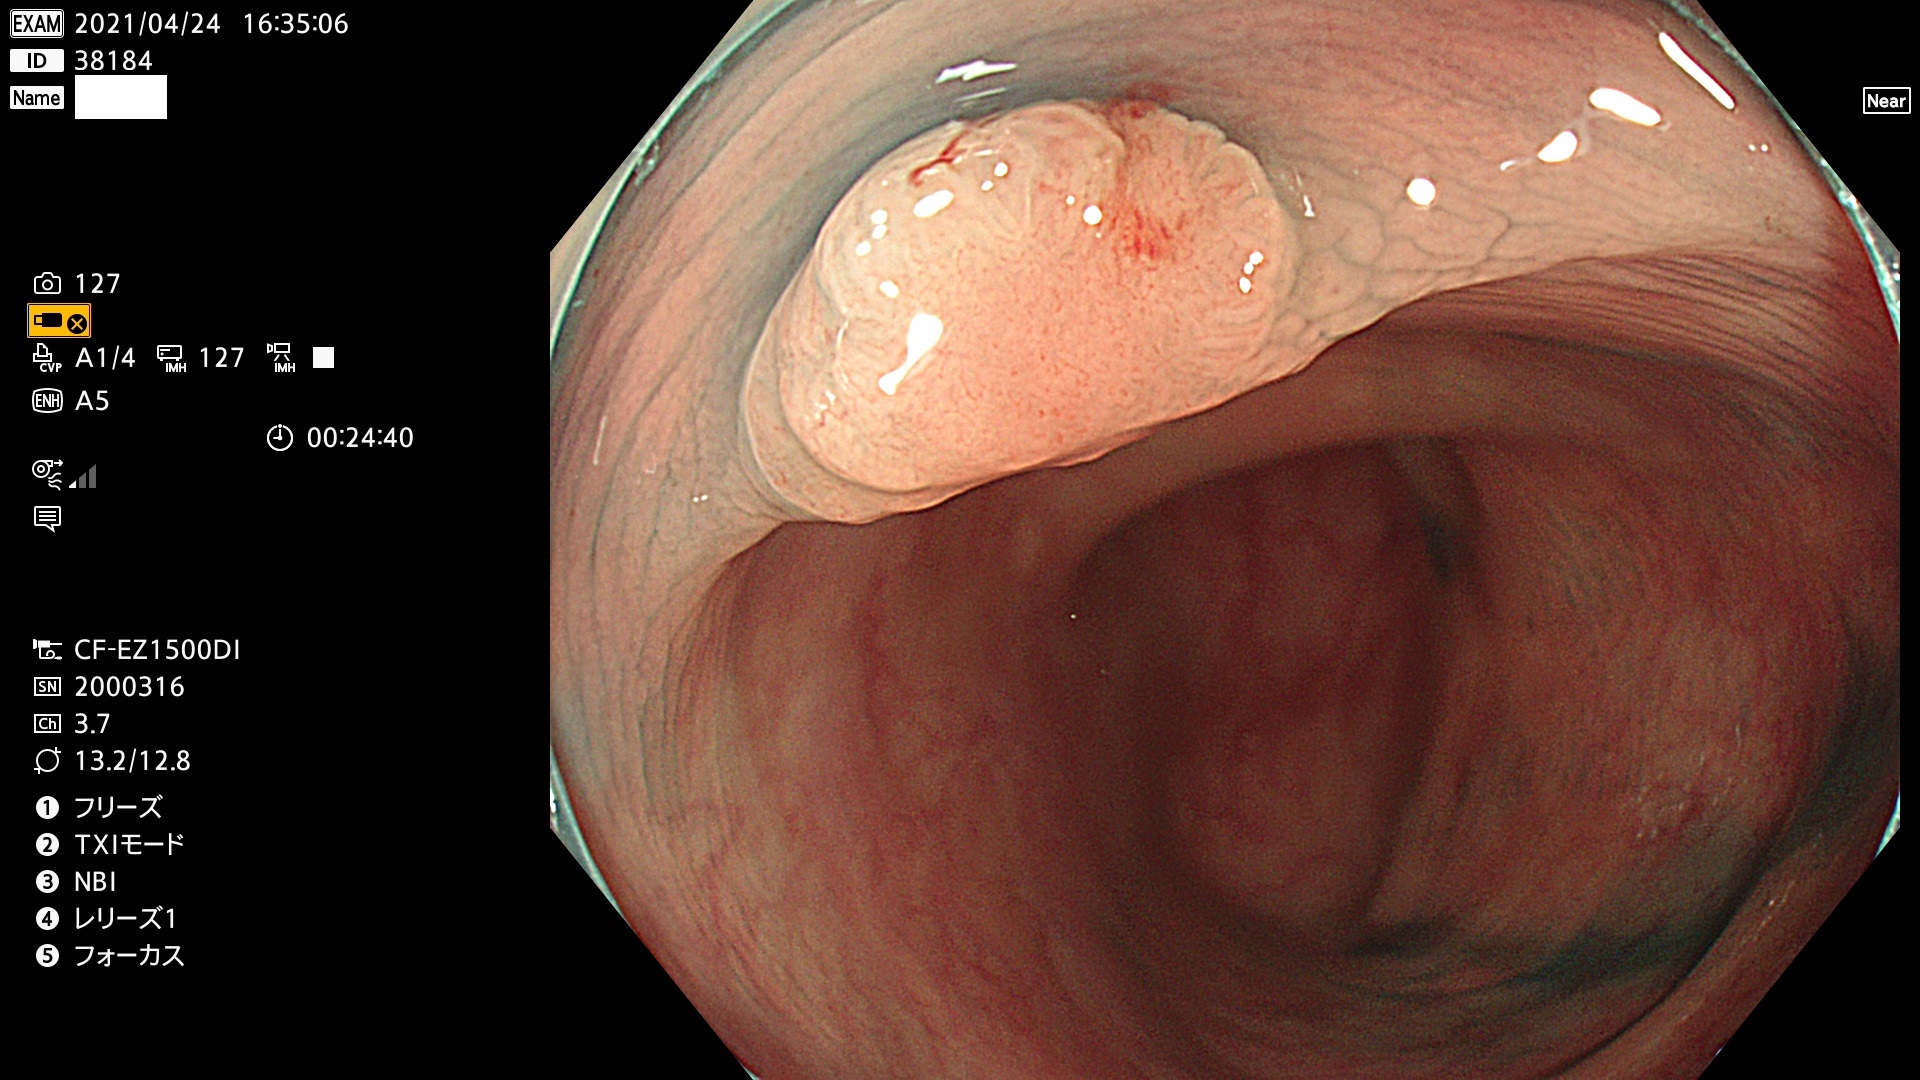

発見困難で危険性の高い平坦型病変(上記100名より抽出) ![]()